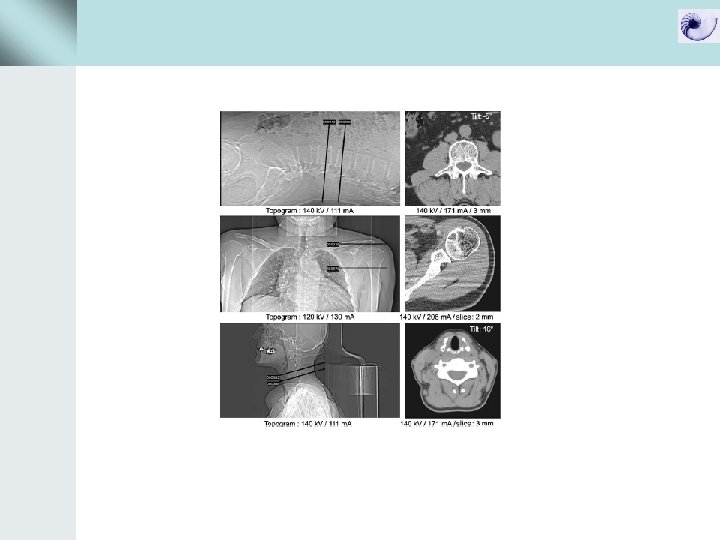

Data acquisition με συμβατικό CT και spiral CT